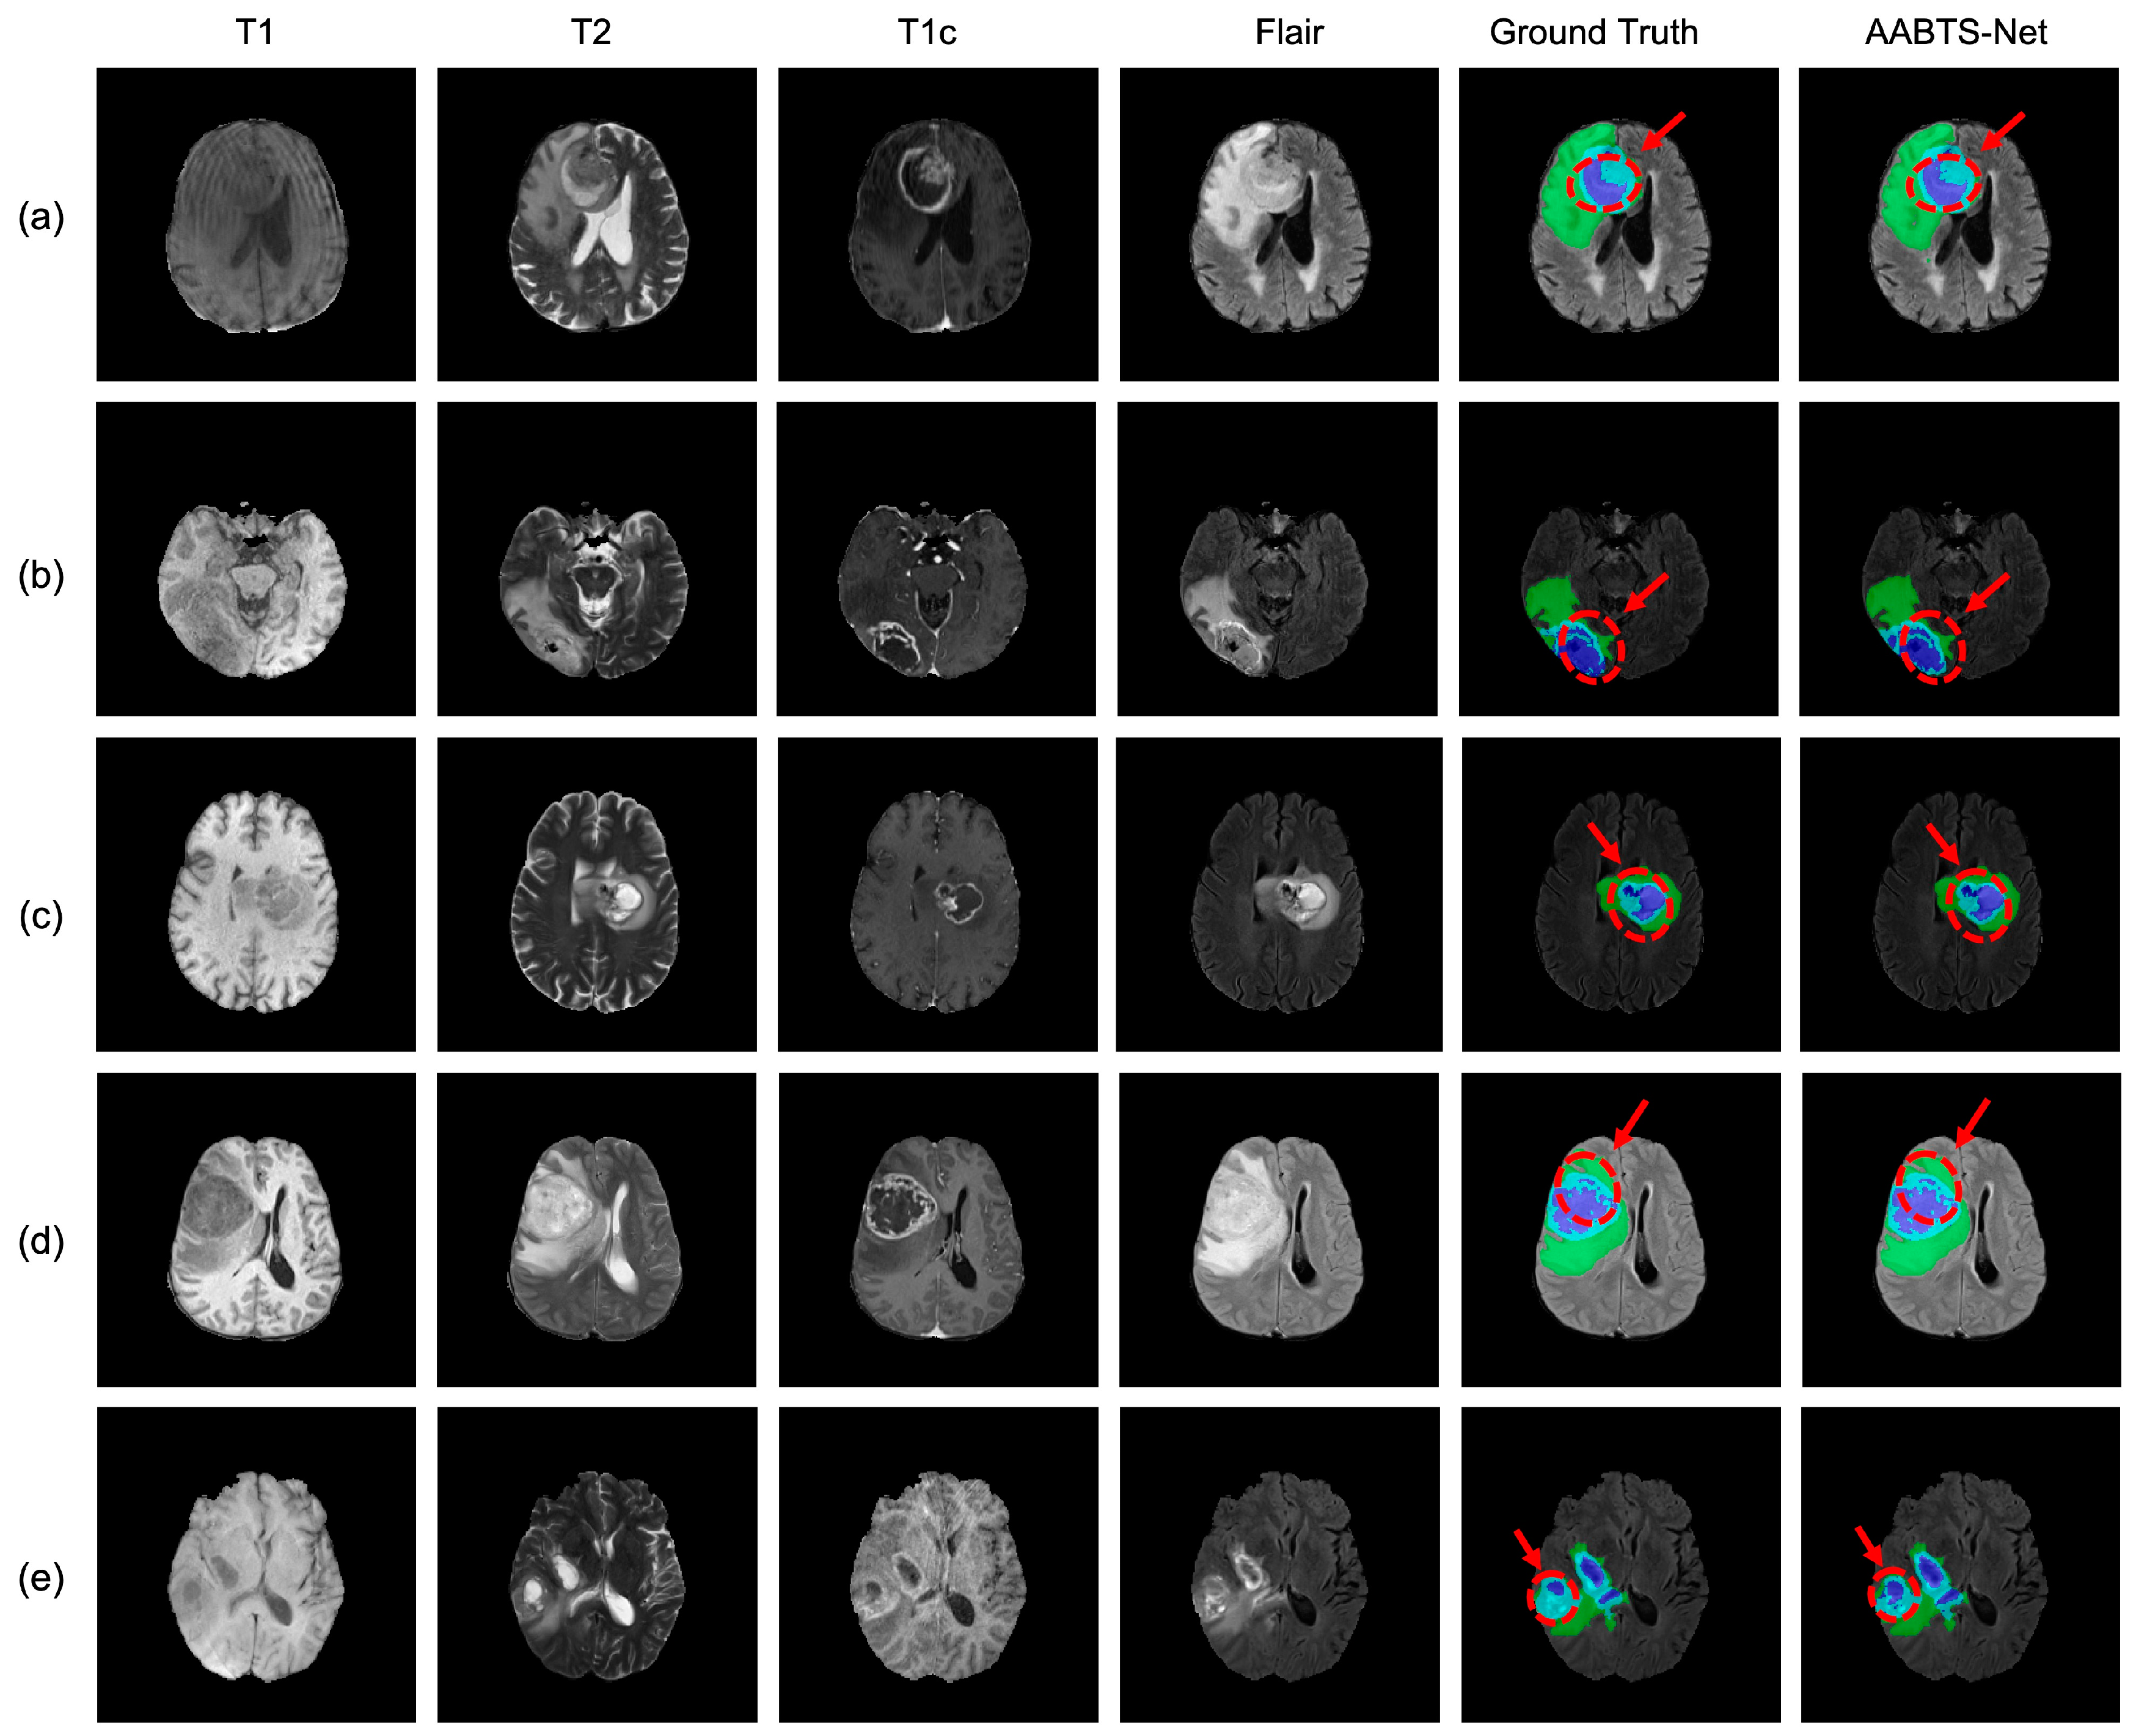

4.3. Analysis of the Bad Tumor Segmentation Results

| Cases | DSC | |||

|---|---|---|---|---|

| ET | TC | WT | AVG | |

| (a) BraTS2021_00493 | 0.885 | 0.924 | 0.270 | 0.693 |

| (b) BraTS2021_00494 | 0.964 | 0.990 | 0.730 | 0.895 |

| (c) BraTS2021_01666 | 0 | 0.738 | 0.916 | 0.551 |

| (d) BraTS2021_01179 | 1.000 | 0 | 0.769 | 0.590 |

| (e) BraTS2021_01293 | 0.541 | 0.929 | 0.874 | 0.781 |